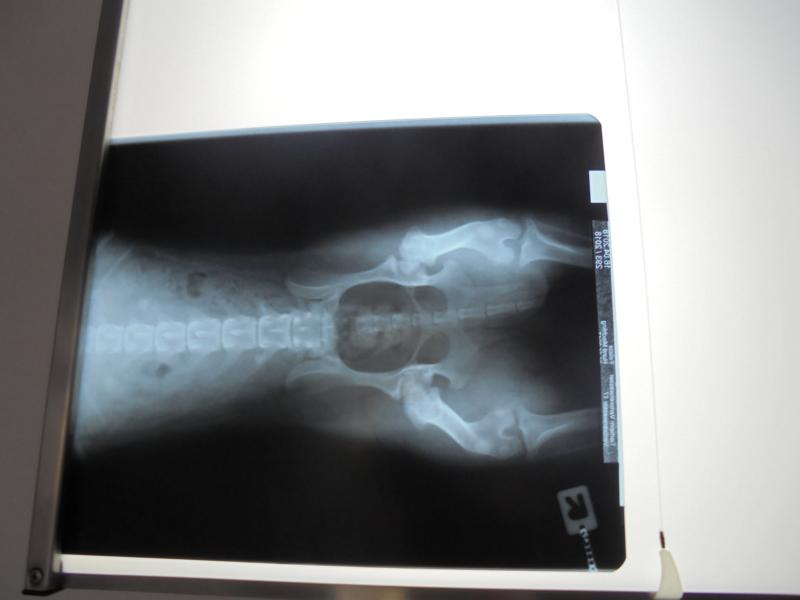

Bei Felicia bestätigte sich der Verdacht, dass beide Hüften operiert werden müssen. Ein ziemlich großer Eingriff - aber Felicia ist ein junges Mädel. Sie wird es wegstecken und ist dann ihre jetzigen Schmerzen los.